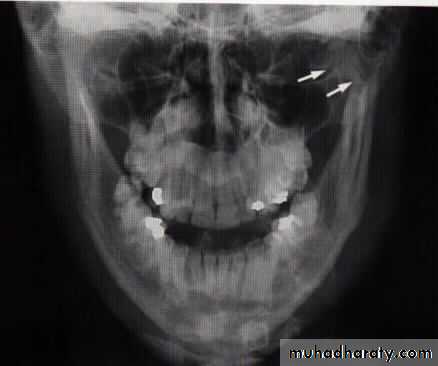

Radiographic evaluation:

Plain radiographOPG

Lateral oblique

PA mandible

AP mandible (reverse Townes)

Lower occlusal

Fracture mandible in children